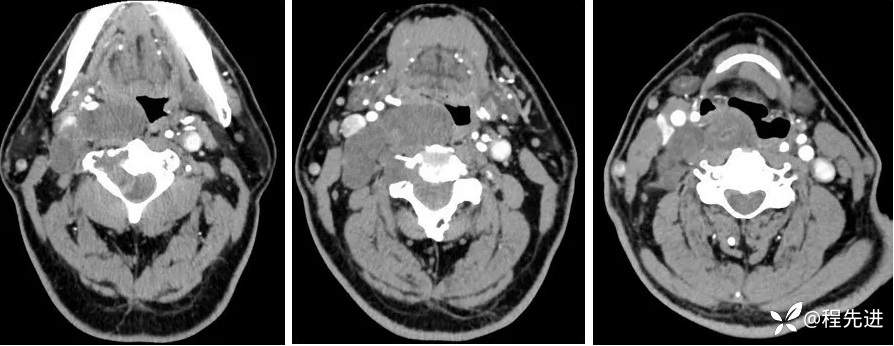

动脉期:

静脉期: